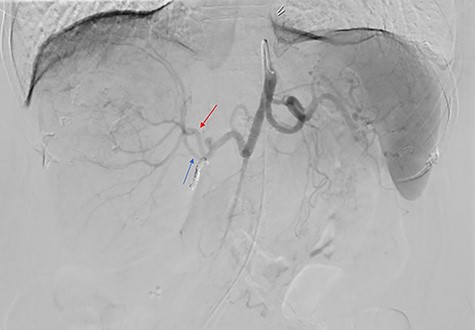

The consensus from the multidisciplinary liver tumor board was to proceed with Y-90 TARE to achieve tumor shrinkage and to induce left liver lobe hypertrophy in preparation for surgical resection. In February 2019, the patient underwent a Y-90 TARE, and a dose of 2.71 GBq (73.4 mCi) of glass microspheres (TheraSpheres, Boston Medical) was injected into the right hepatic artery (Fig. 3). The delivery of the dose was verified using Bremsstrahlung liver SPECT imaging post-injection (Fig. 4). Based on this activity distribution, the dose was calculated on a voxel-by-voxel basis using Sure Plan software (MIM, Cleveland Ohio). The local deposition method (LDM) was used, and the dose was scaled by the amount of activity injected.

Celiac angiogram demonstrated tumor supply from both the anterior (red arrow) and posterior (blue arrow) divisions of the right hepatic artery; the gastroduodenal artery was coiled for embolic protection.